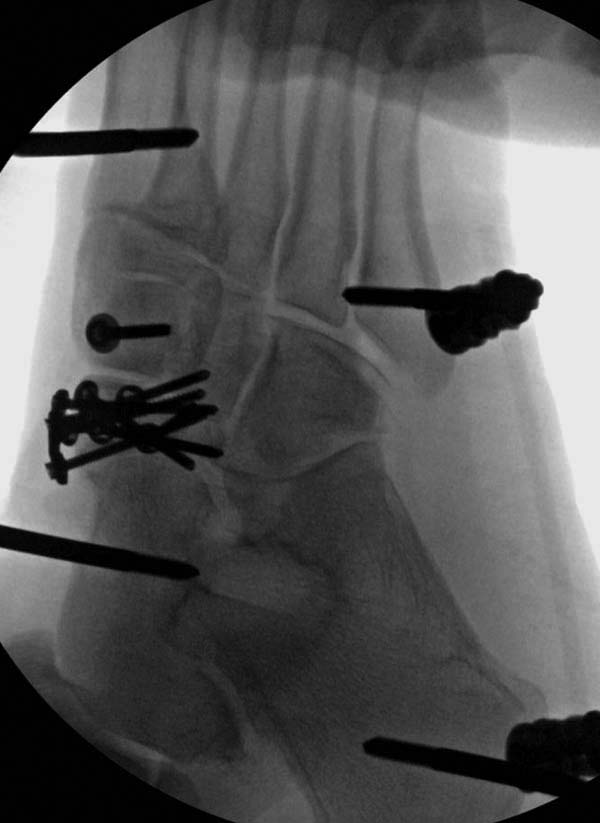

До лечения, в процессе, через 8 мес.

Современную тактику лечения переломов пилона описали коллеги, а мне остается подтвердить клинически. В многоэтапном лечении главное - это предупреждение сокращения мягких тканей, от которого зависит судьба конечности. Дистракция любым наружным фиксатором, и по готовности мягких тканей - премежуточная или окончательная фиксация.

Через три дня повторная I&D, где через рану манипулировали дистальным фрагментом с установкой пары межфрагментарных шурупов. На рану вакуум и следующая обработка закончилась закрытием раны. Отек держался немного дольше, чем обычно.

После спадения отека вариантов фиксации много, включая мининвазивную технику, но данный случай закончили установкой простого аппарата Илизарова.

Через три дня оперирована стопа и для нейтрализации сил колонн оставили наружный фиксатор.

Ещё несколько слов по поводу стратегии и тактики лечения обсуждаемого перелома. Из всех переломов пилона С3, переломы с одновременной деструкций эпифиза, дистального метафиза и нижней трети диафиза большеберцовой кости являются наиболее проблемными при выборе способа финального остеосинтеза. К общепринятому способу остеосинтеза переломов пилона пластинками по медиальной либо латеральной поверхности большеберцовой кости в таких случаях следует относиться критически. Имплантация необходимой длины пластинок (иногда до 20-25 см) требует такой же длины разрезов кожи и мягких тканей, отслоение надкостницы, что ставит на грань разумного их применение из-за возникающих впоследствии тяжёлых осложнений. MIPO (Minimally Invasive Plate Osteosynthesis) крайне сложно реализовать на практике из-за необходимости точной репозиции отломков, имеющих суставную поверхность на уровне эпифиза, и недопустимости угловых деформаций на уровне метафиза и диафиза. Поэтому в последнее время всё большую популярность приобретает комбинированный способ финального остеосинтеза. Если ставить перед собой задачу сохранения сустава, надо исходить из понимания, что дистракция и лигаментотаксис в большинстве случаев переломов пилона не обеспечат репозицию отломков, образующих суставную поверхность. Открытая репозиция неизбежна, так как почти всегда имеются отломки с суставной поверхностью «вбитые» в метафиз. Но открытая репозиция из разрезов длиной 5-6 см должна применяться только для репозиции и фиксации между собой отломков, образующих суставную поверхность. Для этих целей применяются спицы и спонгиозные винты диаметром до 4,5 мм. Реконструированный таким образом дистальный эпиметафиз и проксимальный отломок большеберцовой кости фиксируются спицевым или стержневым аппаратом.

В первом случае после дистракции и КТ было установлено, что дистальный эпифиз состоит из трёх крупных фрагментов, в которых полиаксиально могут быть размещены три блокирующих винта. После открытой реконструкции суставной поверхности, выполненной через трансфибулярный доступ и фиксации отломков, содержащих суставную поверхность спицами, выполнен интрамедуллярный блокированный остеосинтез. Лечение без внешней иммобилизации. Полная нагрузка на ногу – через три месяца.

Второй случай. Не уверен в целесообразности и приемлемости выбранного подхода, но внешние обстоятельства требовали от больной передвижения и полной нагрузки на ногу сразу после операции. Размер костных фрагментов не позволял разместить блокирующие винты в дистальном эпифизе. Была выполнена открытая репозиция перелома из передне-медиального доступа, остеосинтез спицами, интрамедуллярный блокированный остеосинтез с созданием временного артродеза голеностопного сустава. Разрешена полная нагрузка на ногу сразу после операции. Через 3,5 месяца стержень удалён.